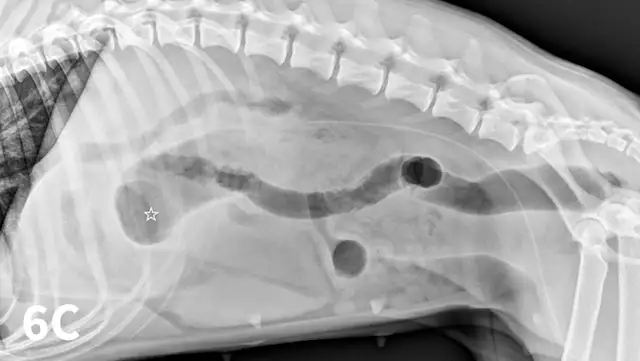

Right and left lateral abdominal radiographs are easy to obtain and are often helpful in cases of suspected GI FBs and obstruction because this positional change shifts the fluid and gas present into different areas, which might highlight potential intraluminal FBs (Figure 5). The main benefit of this simple technique is in the identification of pyloric FBs in cases of suspected pyloric outflow obstruction, but it is also useful in the small intestine, especially if duodenal FBs are suspected.

Figure 5A depicts a left lateral abdominal radiograph of a dog with a pyloric foreign body. Figure 5B depicts a right lateral abdominal radiograph of a dog with a pyloric foreign body.

FIGURE 5

Left lateral radiograph (A) of a 4-year-old crossbreed dog with a 3-day history of vomiting and anorexia. An irregularly marginated, well-defined, soft tissue opaque structure (arrows) outlined by gas is present within the pylorus on the left lateral view. A right lateral radiograph of the same dog (B). The irregularly marginated, well-defined, soft tissue opaque structure displayed in Figure 5A is not clearly seen on the right lateral view because of the dependent distribution of fluid into the pyloric antrum silhouetting with the foreign body. This was confirmed to be cloth causing a gastric outflow obstruction.